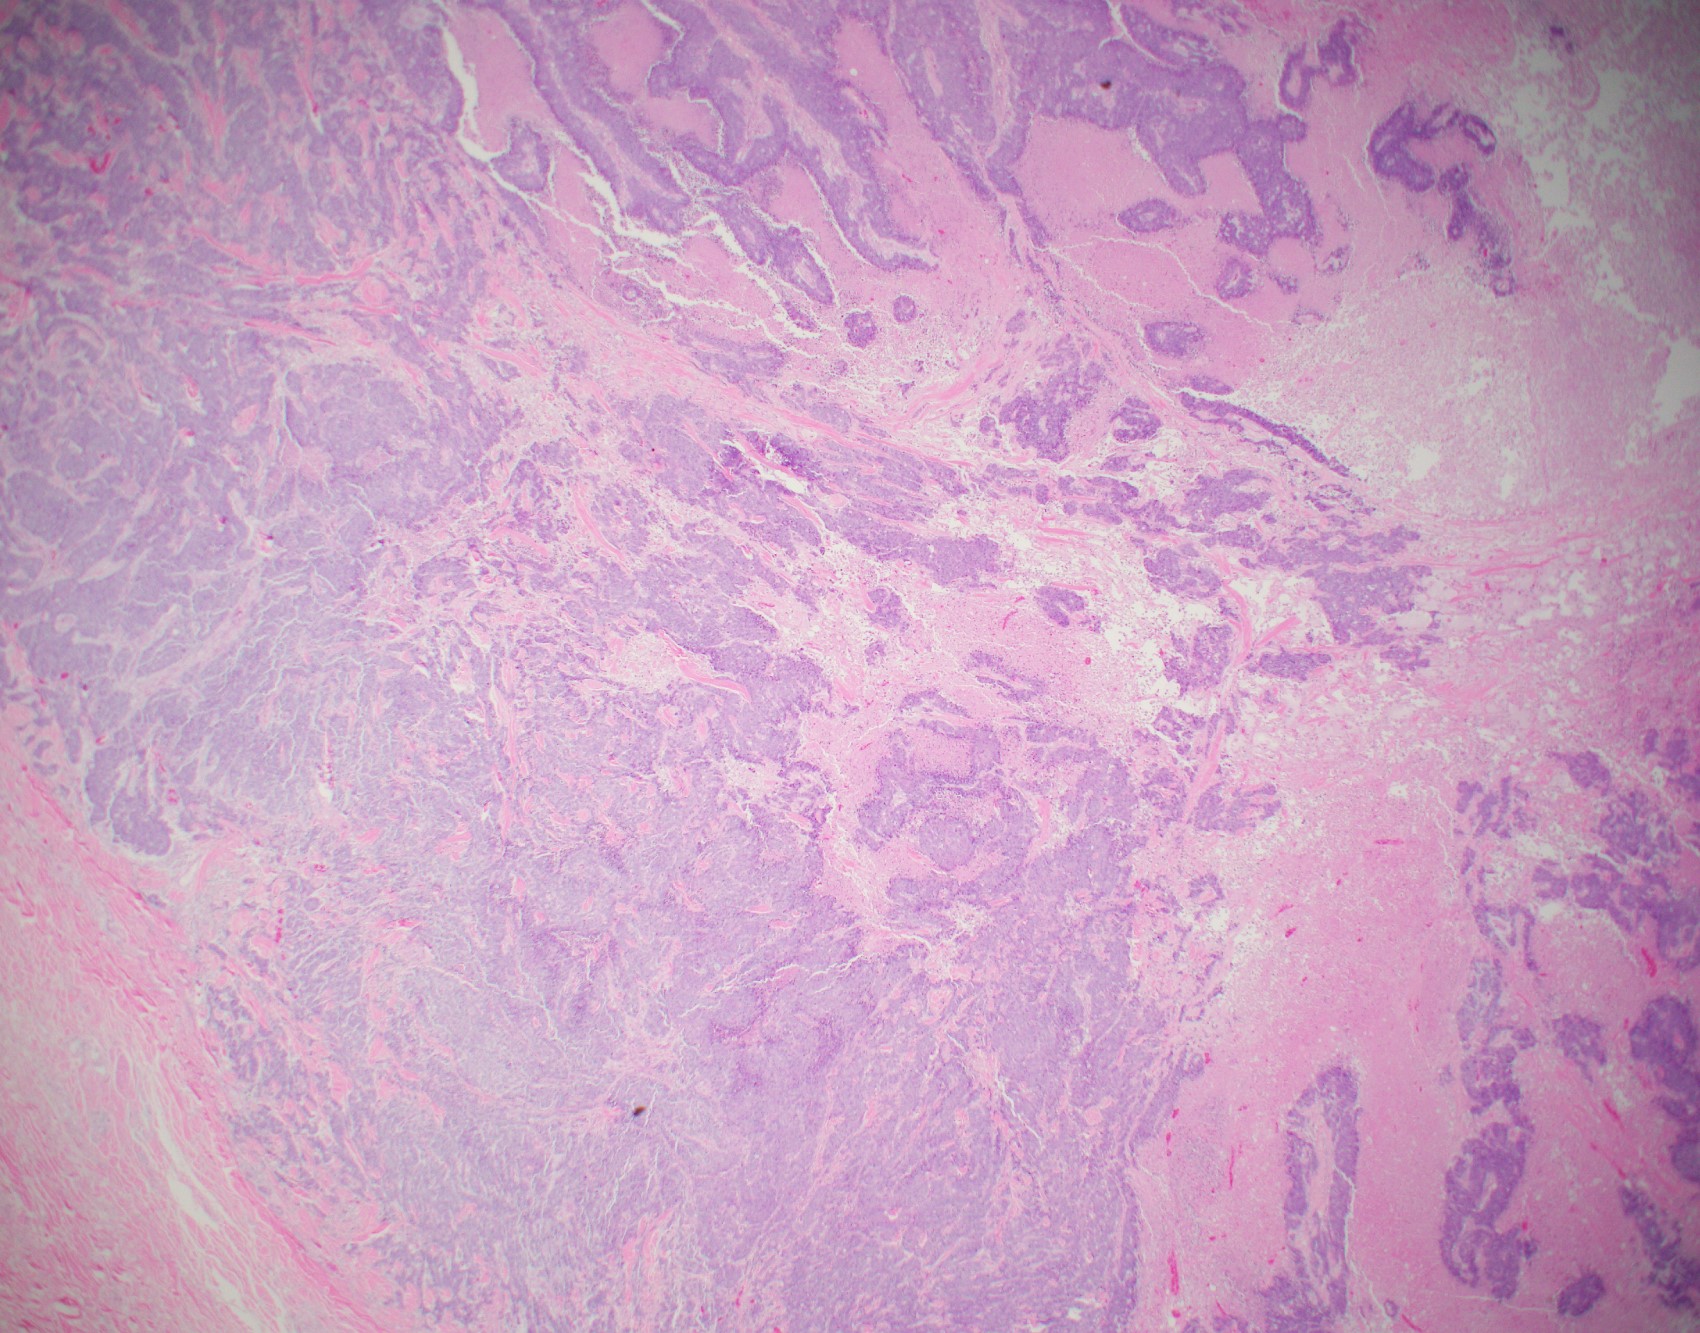

Microscopic (histologic) images

Contributed by Julie M. Jorns, M.D., Kristen E. Muller, D.O., Gary Tozbikian, M.D. and Emad Rakha, M.D.

- Histological features of IBC NST vary considerably from case to case and even within the same case

- Margins vary from highly infiltrative, permeating the surrounding tissue, to continuous pushing margins

- Architecture varies from sheets, nests, clusters, cords or individual cells (but lacks the cytomorphological characteristics of invasive lobular carcinoma)

- 2 distinct growth patterns exist:

- Large and solid nests or syncytial infiltrative growth pattern with little associated stroma and an expansive growth that compresses the surrounding stroma (e.g., most basal-like breast cancers)

- Tumors characterized by small cancer nests accompanied by marked fibrosis (desmoplastic / scirrhous); this type diffusely infiltrates the surrounding tissue as an irregular shaped spiculated mass

- Often ductal carcinoma in situ (DCIS) (up to 80%)